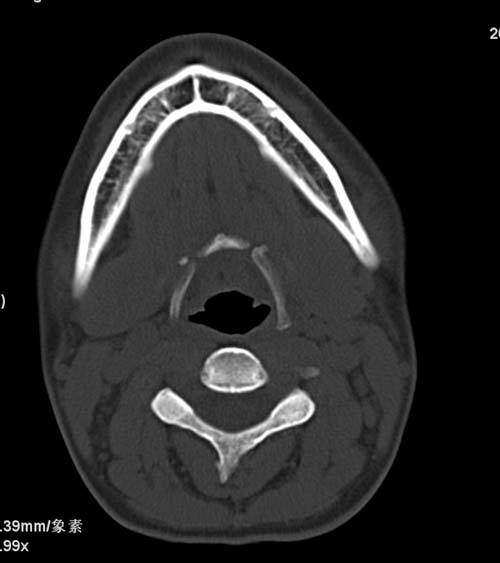

标题: CT22662:女 23 自述双侧颌下腺肿大年余 近来疼痛 左侧明显 [打印本页]

标题: CT22662:女 23 自述双侧颌下腺肿大年余 近来疼痛 左侧明显

见双侧颌下腺略肿大  未见结石及钙化 考虑双侧慢性炎症 ?请指教